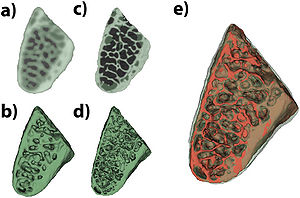

Publication: Sci Rep. 2015 Dec 14;5:18156. PMID: 26657471 | PDF Authors: Hagen CK, Maghsoudlou P, Totonelli G, Diemoz PC, Endrizzi M, Rigon L3, Menk RH, Arfelli F, Dreossi D, Brun E, Coan P, Bravin A, De Coppi P, Olivo A. Institution: University College London, Department of Medical Physics and Biomedical Engineering, London, UK. Background/Purpose: Acellular scaffolds obtained via decellularization are a key instrument in regenerative medicine both per se and to drive the development of future-generation synthetic scaffolds that could become available off-the-shelf. In this framework, imaging is key to the understanding of the scaffolds' internal structure as well as their interaction with cells and other organs, including ideally post-implantation. Scaffolds of a wide range of intricate organs (esophagus, lung, liver and small intestine) were imaged with x-ray phase contrast computed tomography (PC-CT). Image quality was sufficiently high to visualize scaffold microarchitecture and to detect major anatomical features, such as the esophageal mucosal-submucosal separation, pulmonary alveoli and intestinal villi. These results are a long-sought step for the field of regenerative medicine; until now, histology and scanning electron microscopy have been the gold standard to study the scaffold structure. However, they are both destructive: hence, they are not suitable for imaging scaffolds prior to transplantation, and have no prospect for post-transplantation use. PC-CT, on the other hand, is non-destructive, 3D and fully quantitative. Importantly, not only do we demonstrate achievement of high image quality at two different synchrotron facilities, but also with commercial x-ray equipment, which makes the method available to any research laboratory. Funding:

Images acquired with synchrotron-based PC-CT showing a rat small intestine that was decellularized via DET: (a) transverse cross section, (b) three-dimensional view. All scale bars represent 500 μm. Images were processed using the ESRF in-house software PyHST, and analyzed and displayed with ImageJ31 and 3D Slicer. |